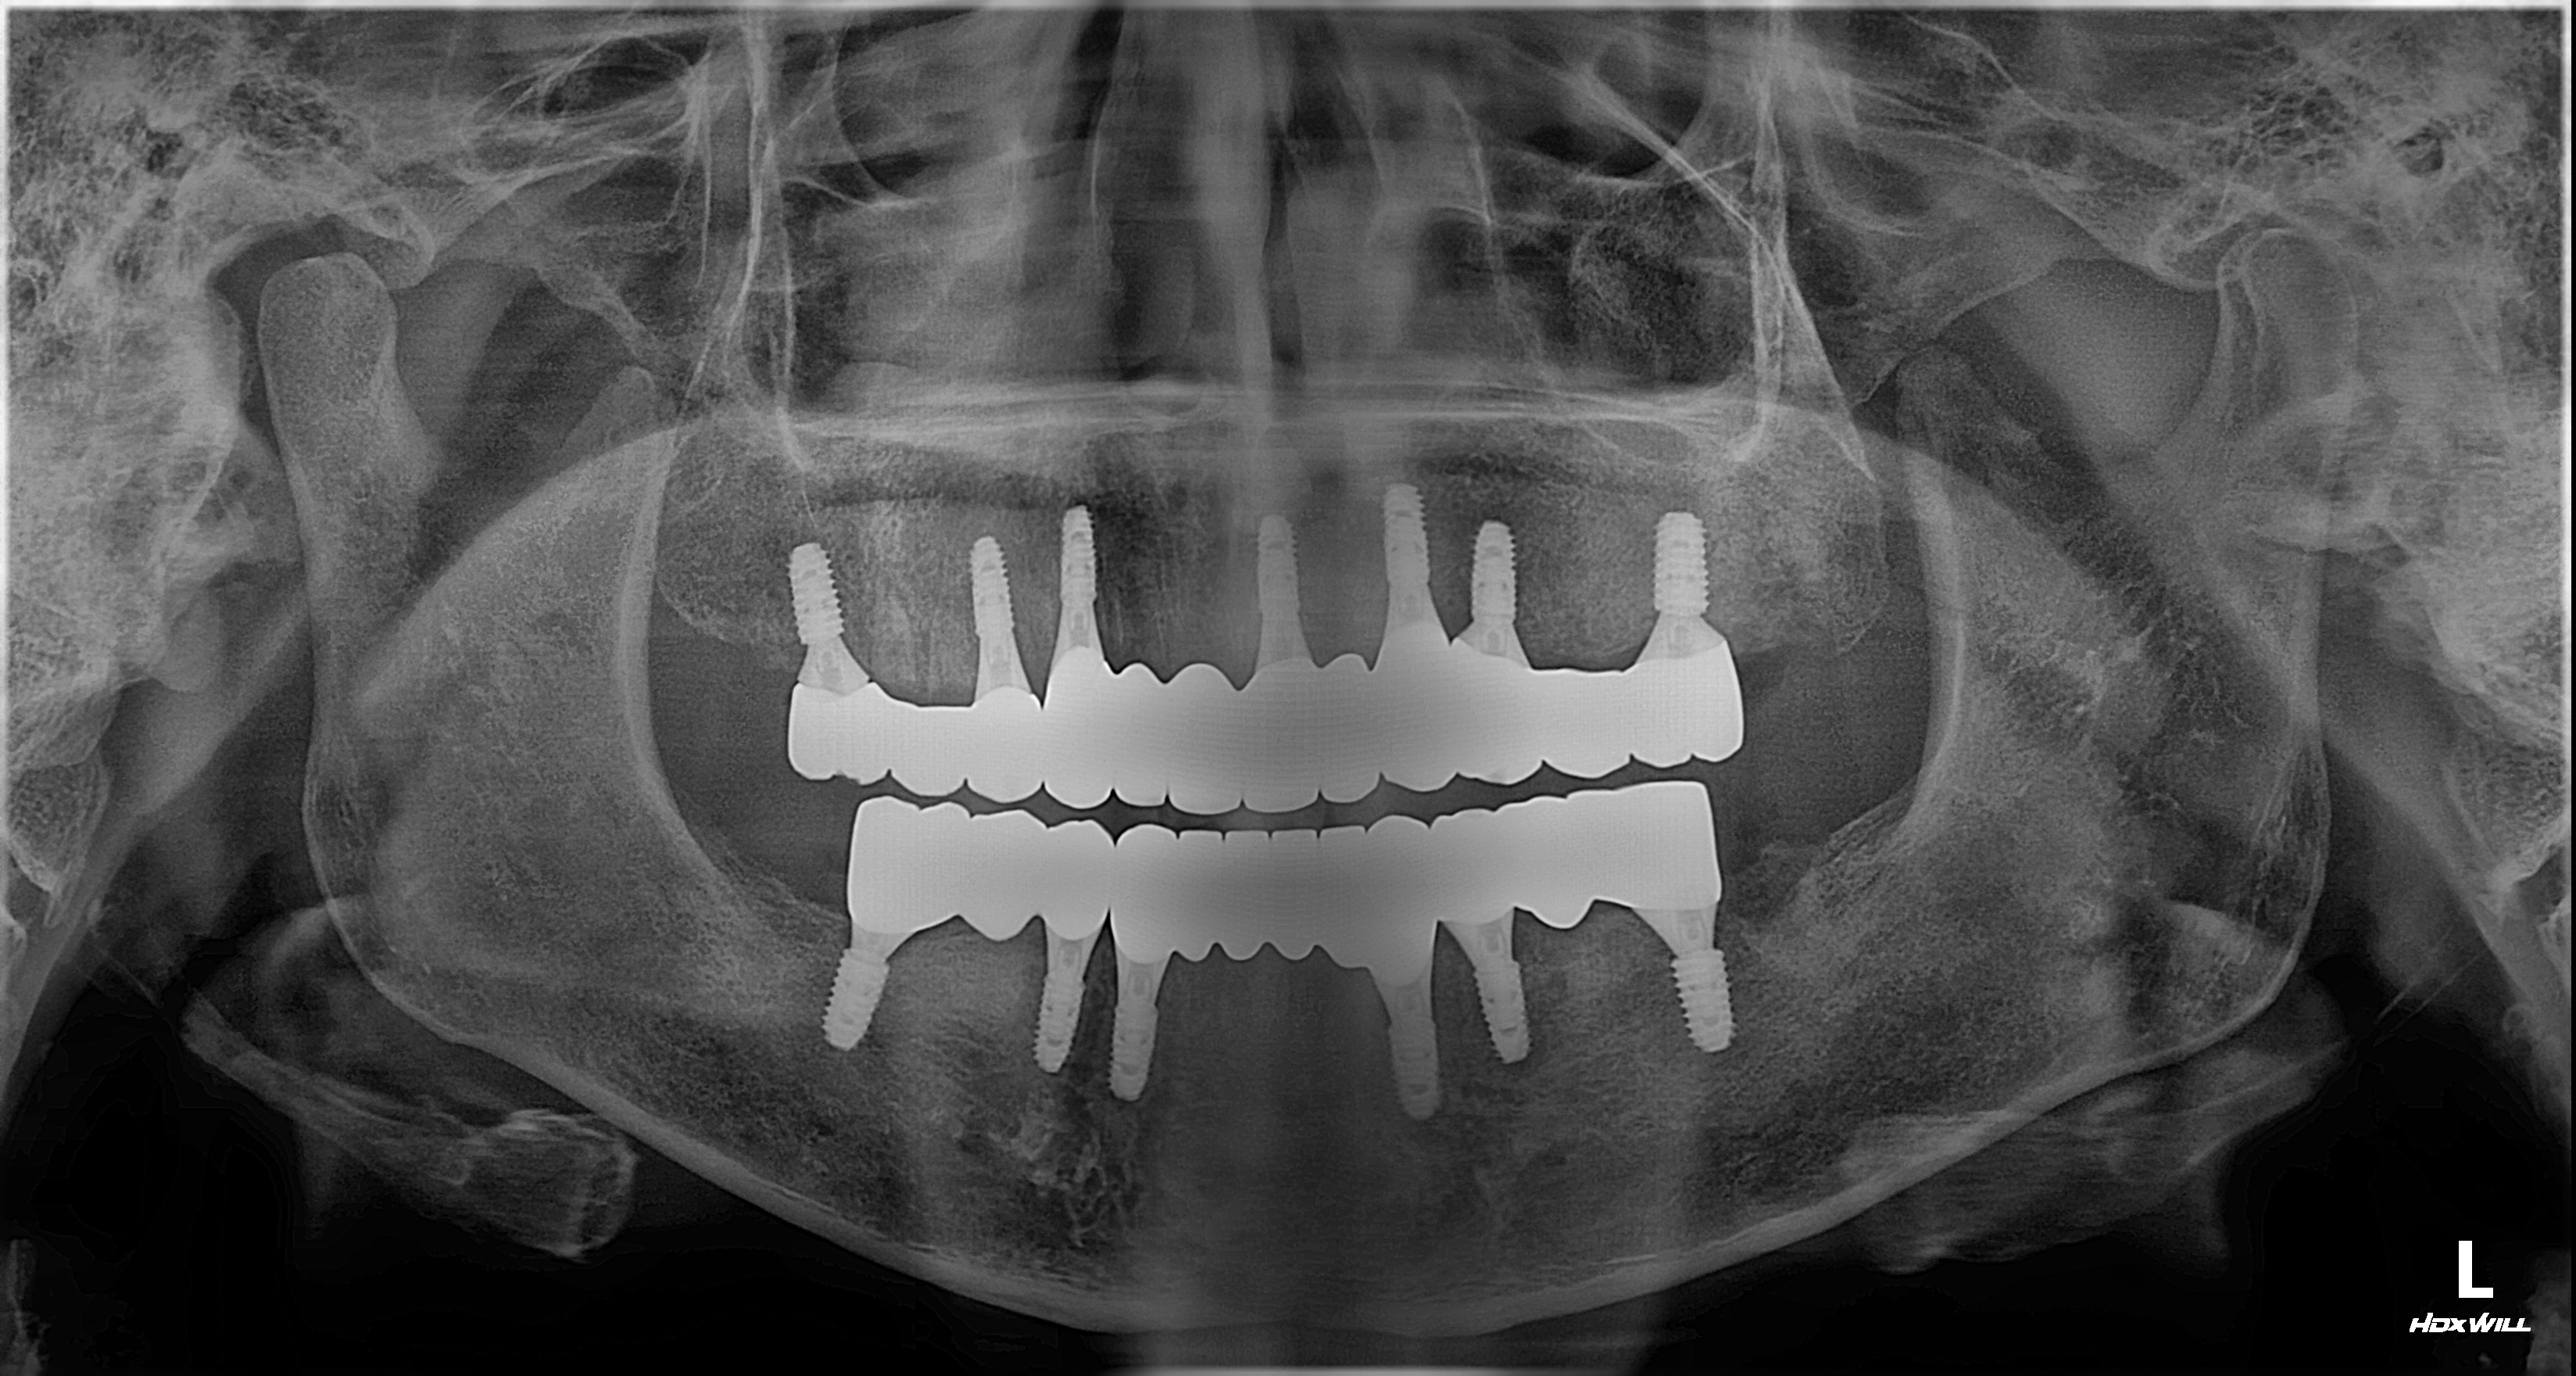

촬영일시: 2025.10.01 [ 치료기간: 2025년 05월 27일 ~2025년 10월 01일 ] ※ 365서울앞선치과의원의 모든 컬럼은 각 진료과 의료진이 직접 작성합니다. 365서울앞선치과의원 임상 케이스 게시물은 환자분께 의학적으로 정확하고 상세한 정보를 드리기 위해 각 진료과 의료진이 직접 작성하며, 모든 증례 사진은 본원 의료진이 직접 시술한 증례를 촬영한 것으로, 의료법 제23조, 제56조에 의거하며 환자분의 동의를 얻어 포스팅에 사용하였습니다. 또한 해당 케이스는 본 환자분의 치료 결과이며, 환자 상태에 따라 치료의 결과는 달라질 수 있습니다. |